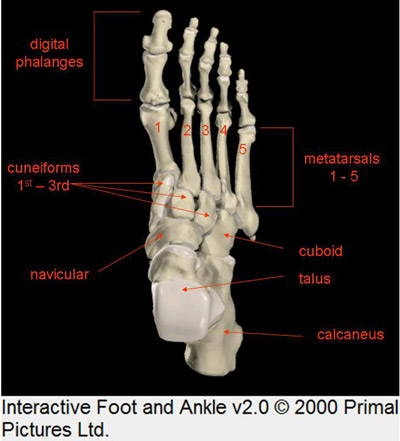

Apareceram hematomas localizados e inchaço. Os locais, foram:

Com melhora em uma semana comecei a apoiar o calcanhar no chão,

o que resultou em recrudescência dos hematomas, edemas, e dores nestas

regiões que irradiavam para os músculos da perna.

abaixo do maléolo medial,

no lado de dentro do pé,

no peito do pé,

no começo dos dedos menores,

e na planta do pé, lugar do "Plexo